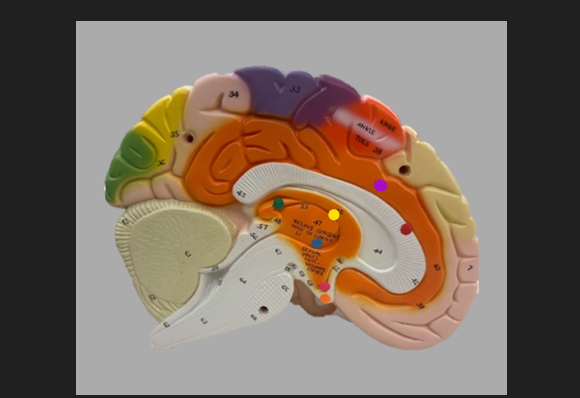

frontal lobe

blue dot

longitudinal fissure

dark green dot

precentral gyrus

pink dot

postcentral gyrus

yellow dot

central sulcus

white dot

parietal lobe

light green dot

Broca’s Area

red dot

Wernicke’s Area

orange dot

occipital lobe

blue dot

parieto-occipital sulcus

blue dot

olfactory tract

red dot

corpora quadrigemina

dark green dot

cerebral aqueduct

blue dot

cerebral penduncles

pink dot

pons

orange dot

medulla oblongata

yellow dot

mammillary body

red dot

corpus callosum

dark green dot

pineal gland

yellow dot

epithalamus

blue dot

thalamus

orange dot

optic chiasm

pink dot

infundibulum

purple dot

cingulate gyrus

yellow dot

pituitary gland

dark green dot

pyramids

red dot

olives

blue dot

optic tract

purple dot

midbrain

green dot

folia

orange dot

arbor vitae

yellow dot

fourth ventricle

red dot

vermis

blue dot

hypothalamus

pink dot

cerebral hemispheres

yellow dot

lateral sulcus

red dot

lateral ventricles

blue dot

hippocampal gyrus